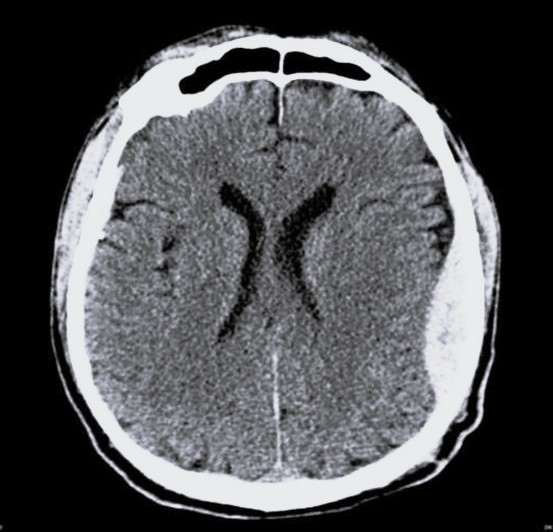

Затемнение на мрт

Затемнение на мрт 140 фото